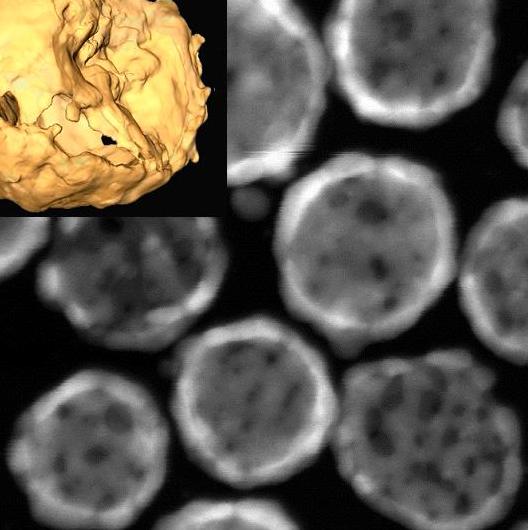

Nanotechnology is the application of nanoscience and, in its modern conception, implies having the ability to design nanomaterials for a specific purpose and to control the manufacturing processes that allow them to have the desired characteristics (composition, size, shape, surface characteristics).

This talk presents the developments in nanotechnology as a true technological revolution. The general concepts and the influence of nanotechnology in our lives shall be discussed with examples of recent advances, with special emphasis on those obtained in the Institute of Nanoscience of Aragon and Unit 9 of NANBIOSIS including with applications in the field of nanomedicine.